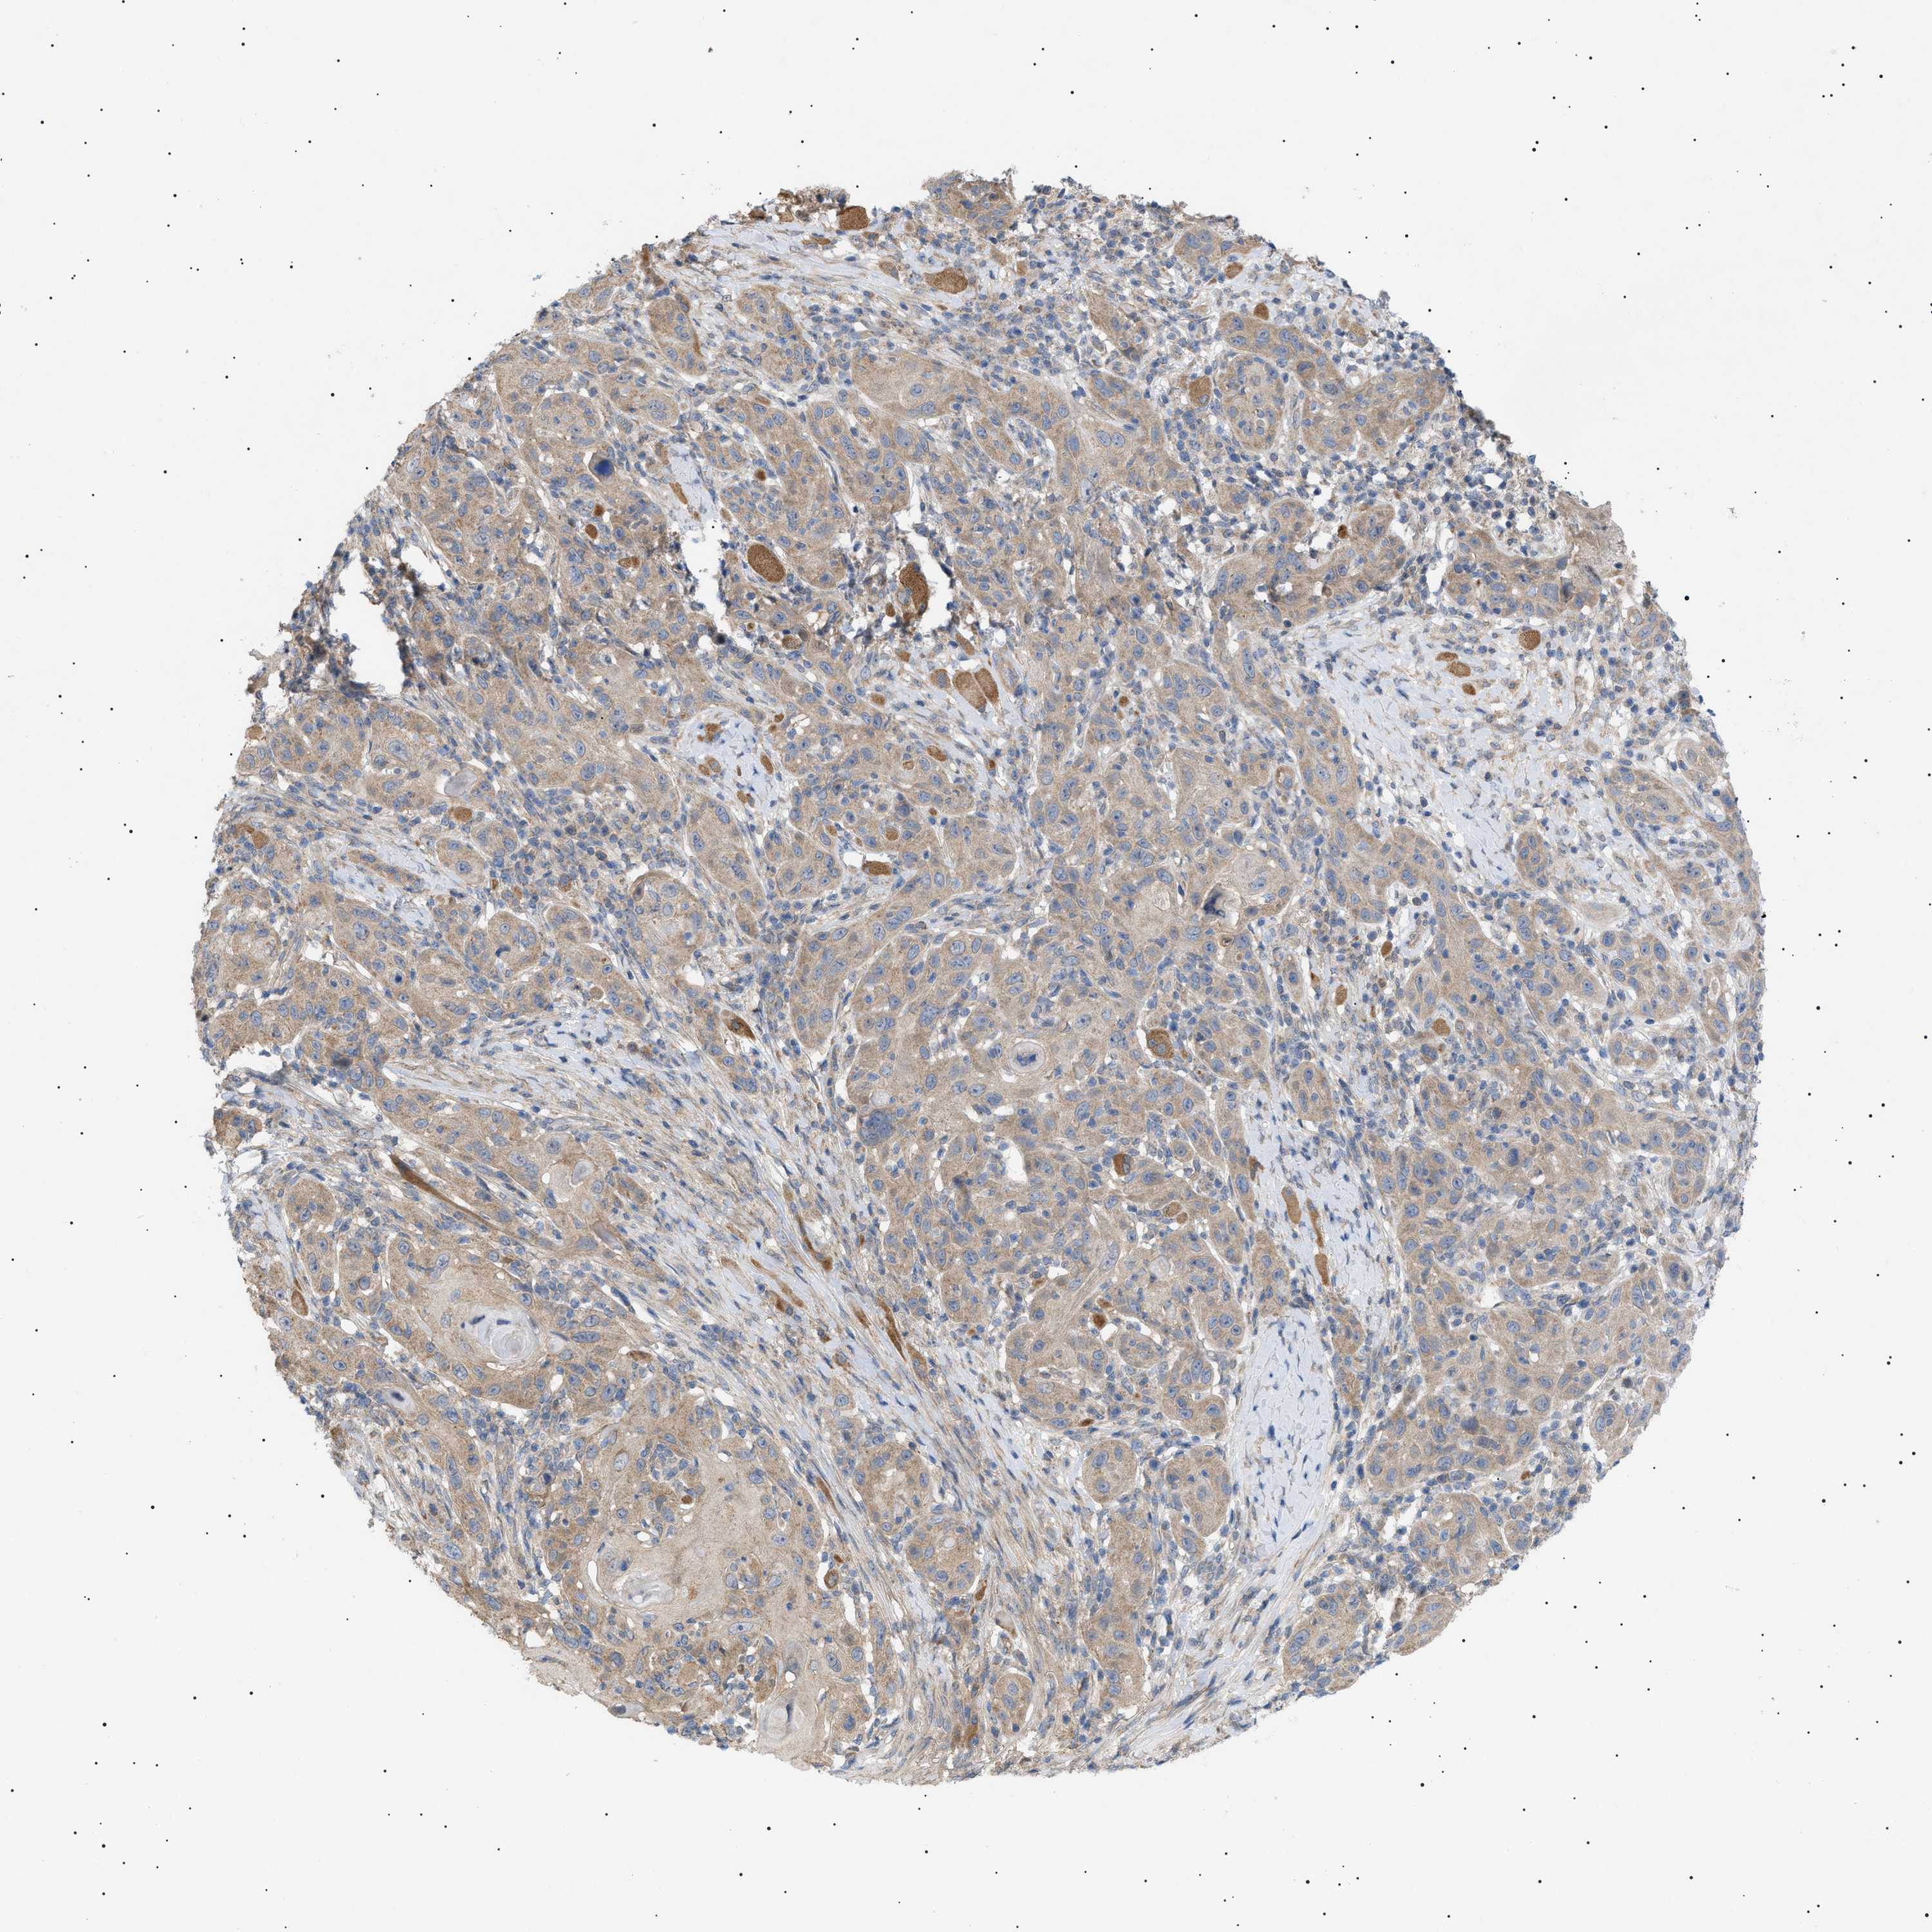

CANCER SKIN CANCER Show tissue menu

SKIN CANCER - Protein expressioni

A mouse-over function shows sample information and annotation data. Click on an image to view it in a full screen mode. Samples can be filtered based on level of antibody staining by selecting one or several of the following categories: high, medium, low and not detected. The assay and annotation is described here.

Each image is clickable and will lead to virtual microscopy that enables deeper exploration of all samples and also displays staining intensity scores, fraction scores and subcellular localization as well as patient and tissue information for each sample.

Antibody CAB016944

Staining

High

Medium

Low

Not detected

Intensity

Strong

Moderate

Weak

Negative

Quantity

>75%

75%-25%

<25%

None

Location

Nuclear

Cytoplasmic/membranous

Cytoplasmic/membranous,nuclear

Squamous cell carcinoma, NOS